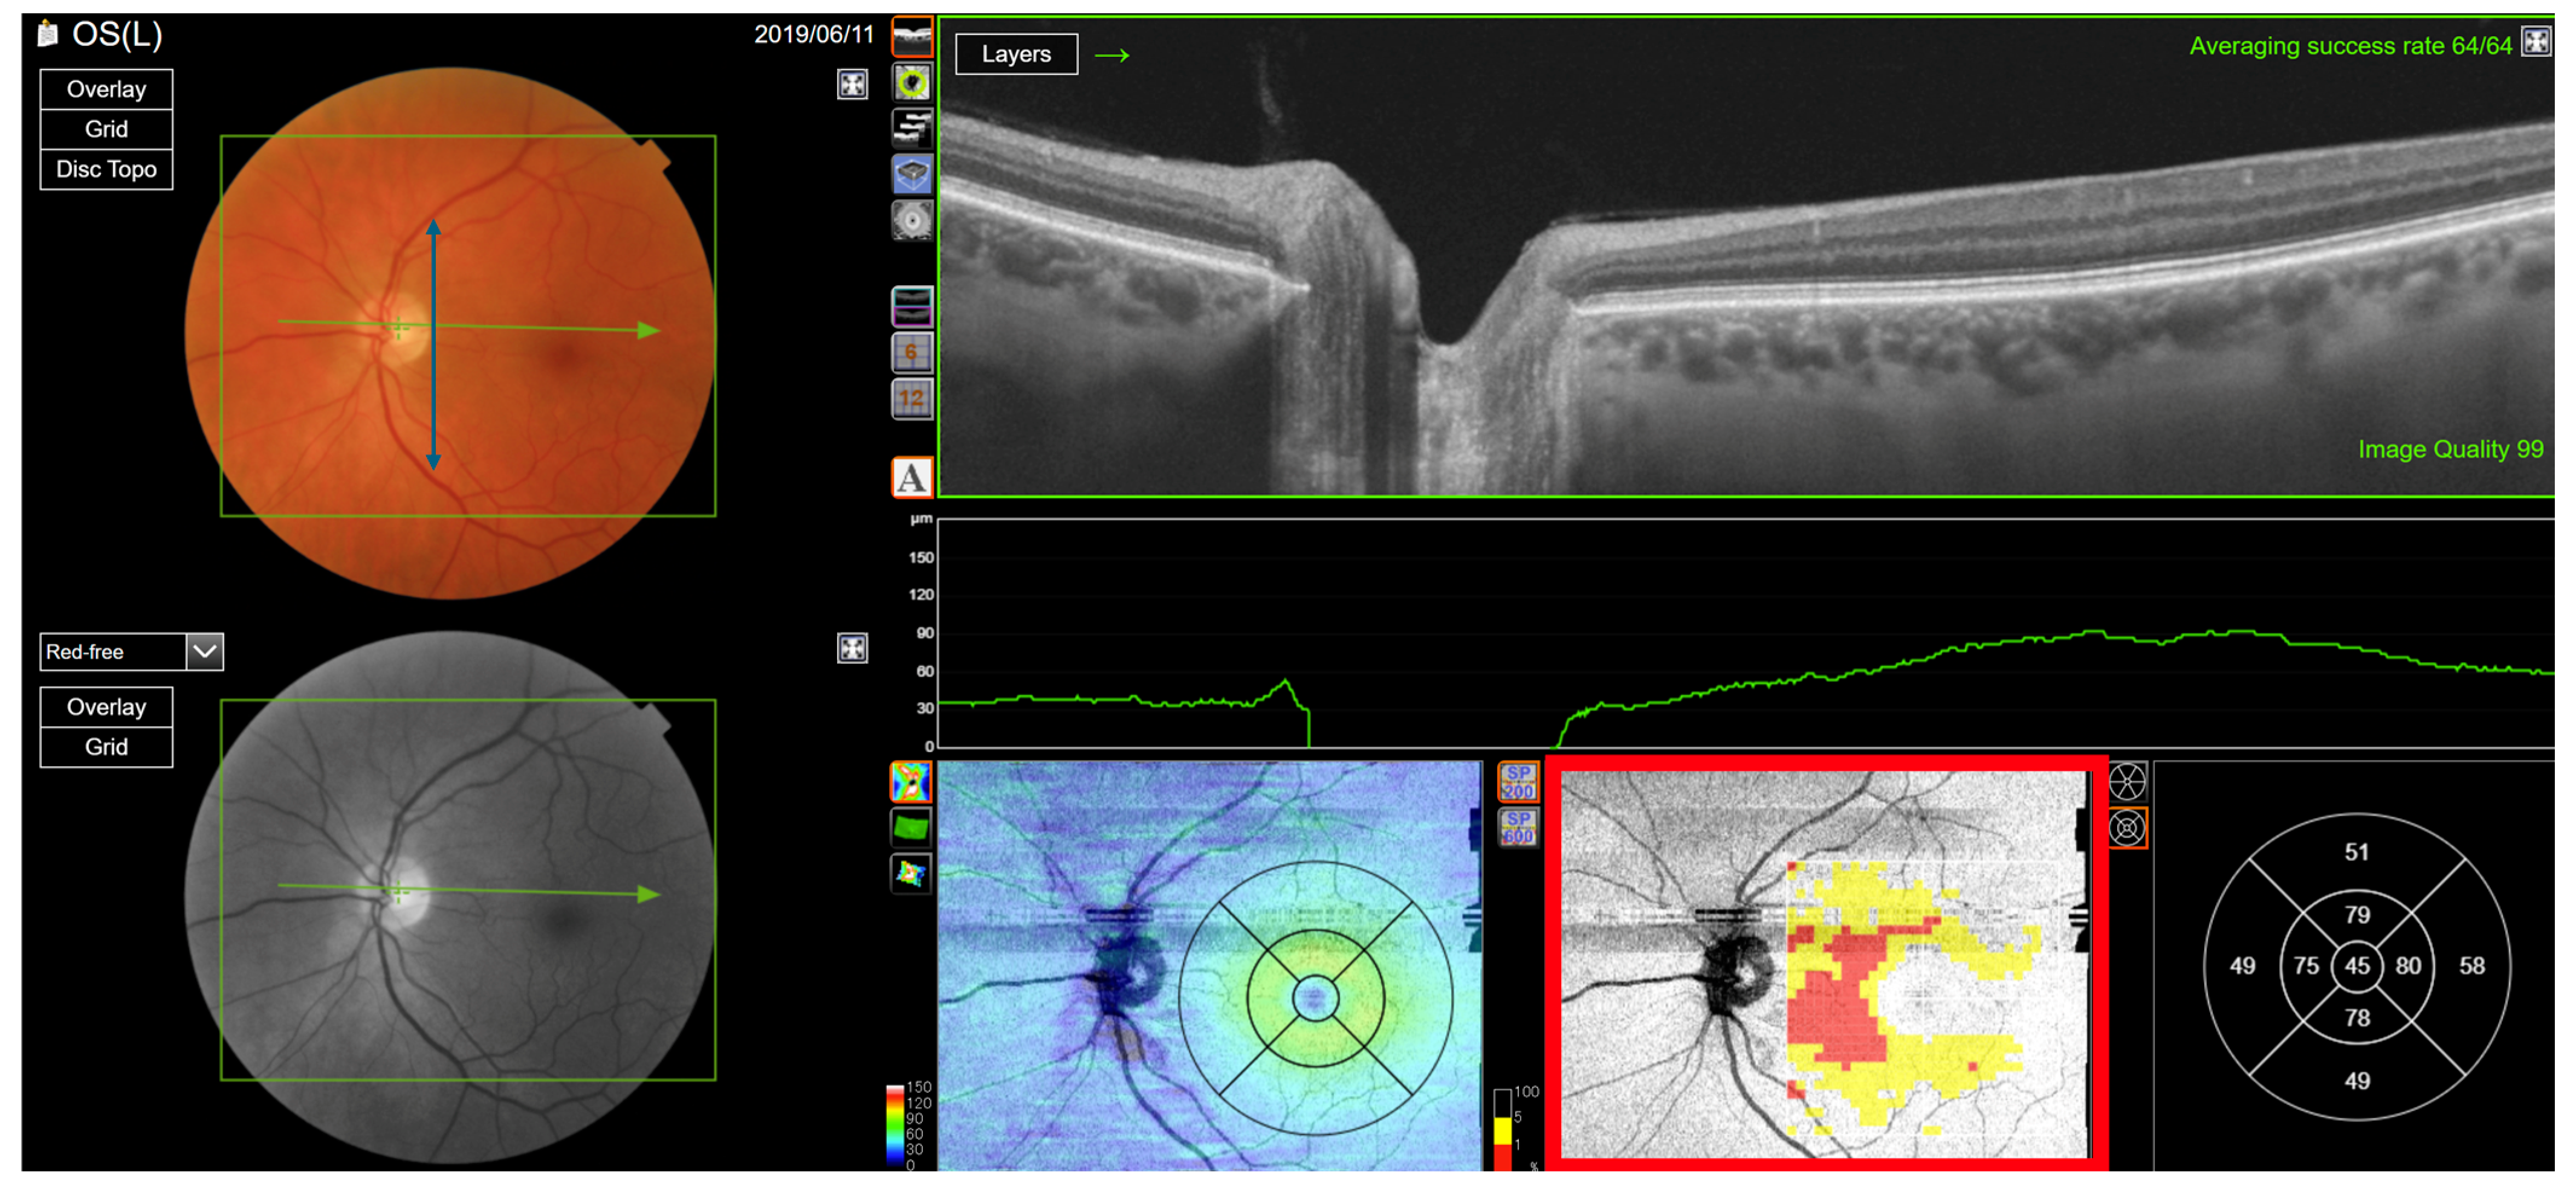

Figure 13. Ganglion cell layer analysis of a healthy left eye with a wide macula. The vessel separation angle is wide (blue double arrow). The ganglion cell layer is thin at the centre of macula, except at the rim of the fovea (red rectangle).

A correlation between RNFL- and GC-IPL-based classifications was seen in that the 26 (34%) out of the 77 eyes with type 6 annular clusters were RNFL type 2 eyes with a wide RNFL ridge separation angle (Table 7), thus showing that when the separation angle is wide, the macula tends to be thinner (Figure 13). When the separation angle is narrow, the centre thickness of the macular centre tends to be normal compared to the reference group (Figure 14).